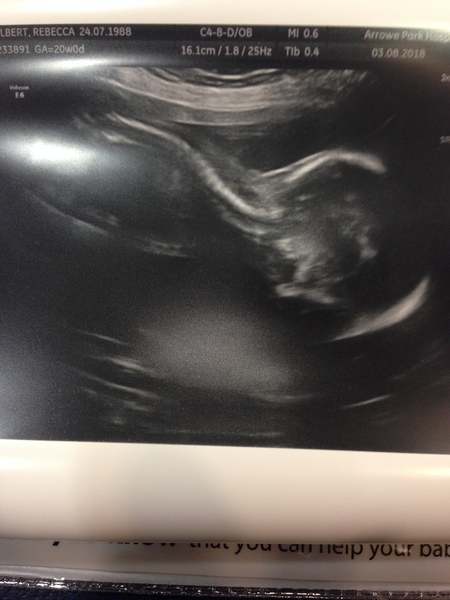

I'm finally starting to feel like this is actually happening.